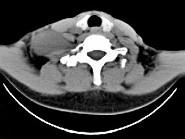

问题 女,47岁,下颈部触及一包块约五年余,CT如图所示,最可能诊断为 ( )

选项 A、副神经节瘤 B、巨淋巴结增生症 C、血管瘤 D、神经鞘瘤 E、滑膜肉瘤

答案 D